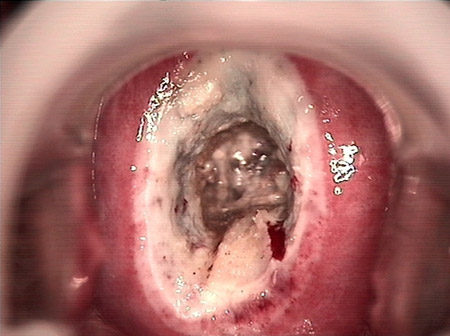

婦科leep錐切手術(shù) CIN2-3

• CIN 2-3 leep術(shù)后CIN 2-3 leep術(shù)后